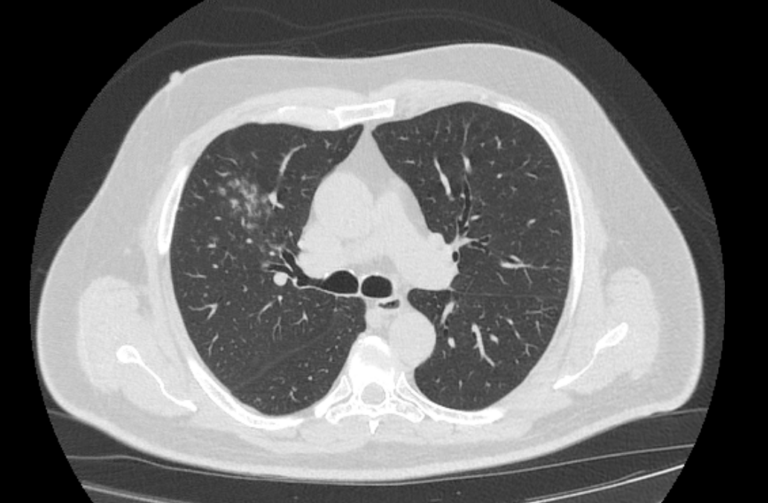

Во время исследования рентгеновская трубка томографа вращается вокруг исследуемой области и производит множество послойных снимков с шагом 0,5-1 мм. Полученные снимки поперечного сечения с помощью компьютерной программы могут быть преобразованы в 3D-изображения исследуемого органа или участка ткани. Это позволяет выявлять практически все заболевания легких на ранних стадиях и назначать своевременное лечение.

В медицинском центре «Доступная медицина» используется современный 128-срезовый компьютерный томограф TOSHIBA AQUILION CXL, на котором проводится сканирование легочной ткани. За счет увеличенного количества детекторов аппарат производит снимки с большой скоростью и минимальной дозой облучения. При этом инновационные цифровые приложения позволяют получить объемные изображения легочной ткани высокой четкости, контрастности и в мельчайших подробностях.